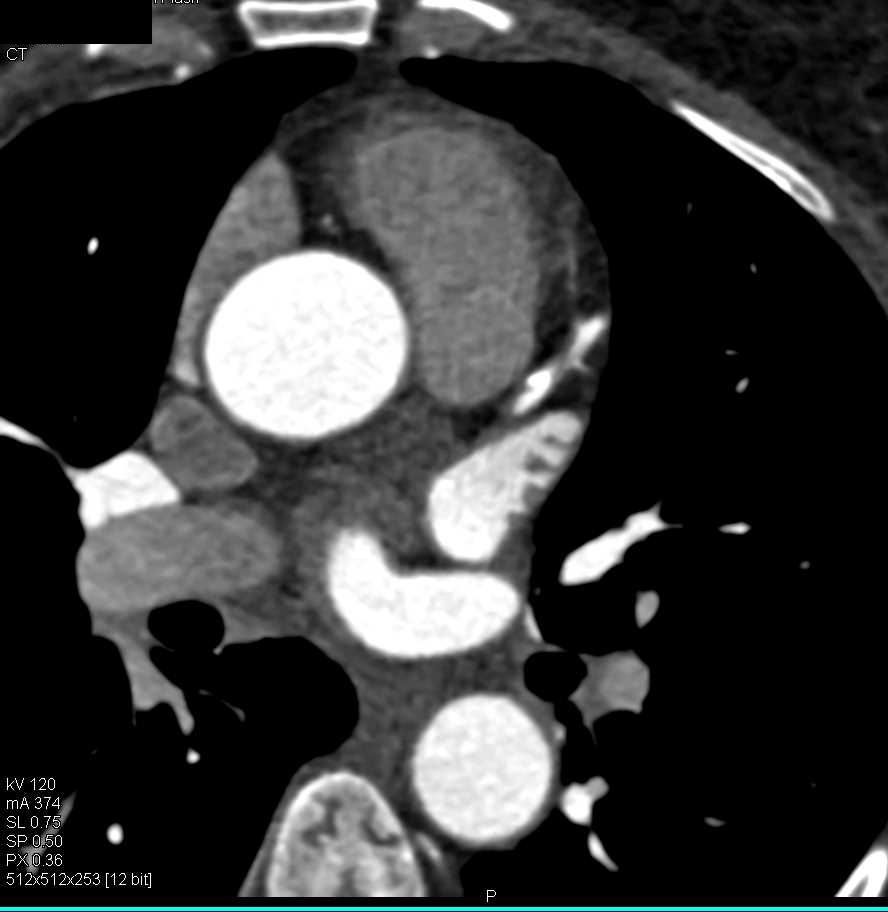

Left Atrial Myxoma